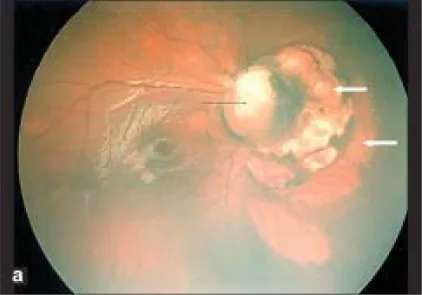

脈絡網膜ラクナ

分布:両側性。乳頭周囲・後極に密集するが、周辺部にも及ぶ。

外観:円形〜楕円形の黄白色〜ピンク色病変。有病率は70〜90%1)。

組織学:網膜色素上皮(RPE)の欠損が脈絡膜層から裸の強膜層に至る2)。

経過:術後に経時的にサイズや数が増大する場合がある2)。

本疾患の眼科的所見のうち、脈絡網膜ラクナは本疾患に病的特異的(pathognomonic)な所見とされる。

脈絡網膜ラクナ

分布:両側性。乳頭周囲・後極に密集するが、周辺部にも及ぶ。

外観:円形〜楕円形の黄白色〜ピンク色病変。有病率は70〜90%1)。

組織学:網膜色素上皮(RPE)の欠損が脈絡膜層から裸の強膜層に至る2)。

経過:術後に経時的にサイズや数が増大する場合がある2)。

脈絡網膜ラクナの組織学的特徴として、網膜色素上皮(RPE)の欠損が脈絡毛細血管板から裸の強膜層に至ることが確認されている2)。欠損部位には網膜色素上皮および脈絡毛細血管板が存在せず、未分化な神経網膜の異形成が認められる。